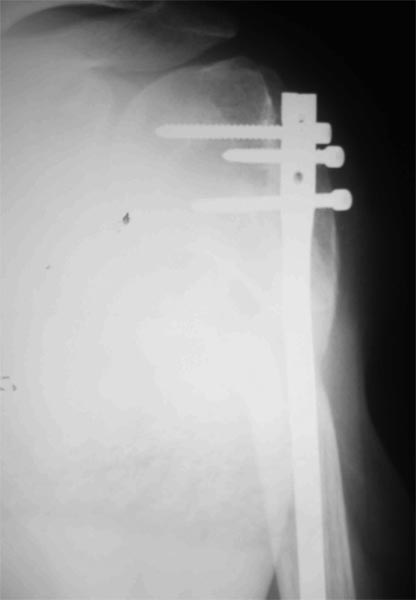

Уважаемые коллеги! Пациент получил травму около 1 года назад, выполнялся остеосинтез по поводу переломов лучевой, бедренной, плечевой костей.

Обратился в связи с выраженной контрактурой в коленном суставе (сгибание 10-15 град)и практически отсуствием самостоятельного отведения плеча. Снимки представлены. Планируем выполнить реостеосинтез плеча (скорее всего этим же стержнем, так как другого нет) с коррекцией положения отломков в проксимальном отделе и сближением отломков в области диафиза.

- адекватен ли по Вашему мнению реостеосинтез стержнем?